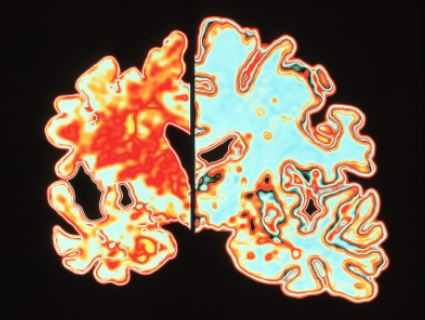

МРТ головного мозга. Демонстрация атрофии и нормы при цветовой обработке.

Болезнь Альцгеймера - прогрессирующее нейродегенеративное заболевание, характеризующееся постепенным развитием деменции. Происхождение заболевания точно неизвестна. Биохимические изменения состоят в снижении активности холин-ацетил-трансферазы коры головного мозга и гиппокампов. Патологические проявления заключаются в образовании специфических амилоидных бляшек, нейрофибриллярных тяжей и реактивном глиозе. Развивается атрофия, захватывающая преимущественно кору вокруг Сильвиевых щелей и гиппокампы, с вторичным расширением желудочков, особенно височных рогов

Частота составляет 0,51% для лиц в возрасте 70-74 лет с возрастным прогрессирующим увеличением частоты. Клинические проявления состоят в нарушении памяти, депрессии, поведенческих нарушениях и галлюцинациях. На поздних стадиях к психическим расстройствам добавляется экстрапирамидная симптоматика. Заболевание занимает 4 место по смертности. Диагноз ставится на основании клинического и нейрофизиологического обследования, а также нейровизуализации. Типичные проявления на КТ состоят в диффузной атрофии (особенно,височных долей), вторичном расширении борозд и желудочков. Чувствительность КТ (без измерения объемов) в сравнении с нормальной возрастной группой около 80%, специфичность около 70%. Измерение объемов гиппокампов при выполнении МРТ с тонкими срезами повышает точность до 85%.

МРТ головного мозга служит метода выбора оценки структурных изменений. Атрофические изменения выражены во всём медиобазальном отделе височной доли. Чувствительность и специфичность МРТ при начальной деменции около 80%. Измерение объемов гиппокампов и амигдалы повышает точность до до 85%.

МРТ головного мозга. Т1-взвешенная корональная МРТ. Диффузная атрофия при болезни Альцгеймера.